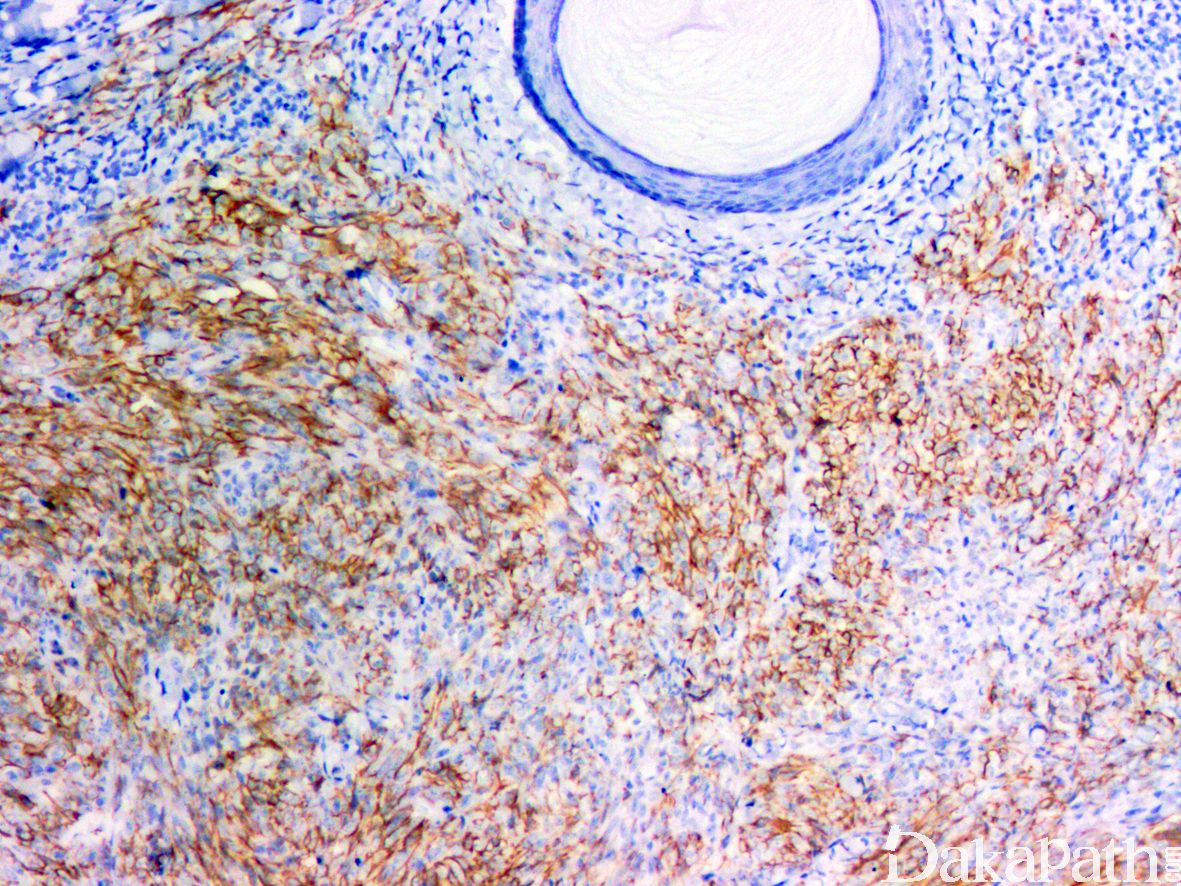

2,肿瘤位于浅表真皮或皮下,直径 0.8-8.5cm(平均 3cm),镜下肿瘤的整体上呈推挤状浸润性生长,边界周围和肿瘤内可见较多而致密的淋巴细胞浸润,有时可见生发中心形成;

肿瘤由分支状的血管腔隙被覆鞋钉样立方状内皮组成,内皮细胞核圆形深染,胞浆稀少,核可见折叠、核裂以及核内包涵体;

低倍镜下部分区域类似于网状血管内皮细胞瘤,表现为血管腔隙受压,被覆鞋钉样内皮以及管周纤维化增生,但管腔并不伸展,较短,类似于裂隙状微腺泡;异型性较大的细胞呈圆形

表达 CD31 和 ERG,65%表达 CD34;至少表达 D2-40. Prox-1 以及 LYVE-1 三个淋巴管标志物中其中的 1 个;通常弥漫表达 D2-40 和 Prox-1,半数表达 LYVE-1。背景中的淋巴细胞主要是 CD4 和 CD8 阳性的 T 淋巴细胞。